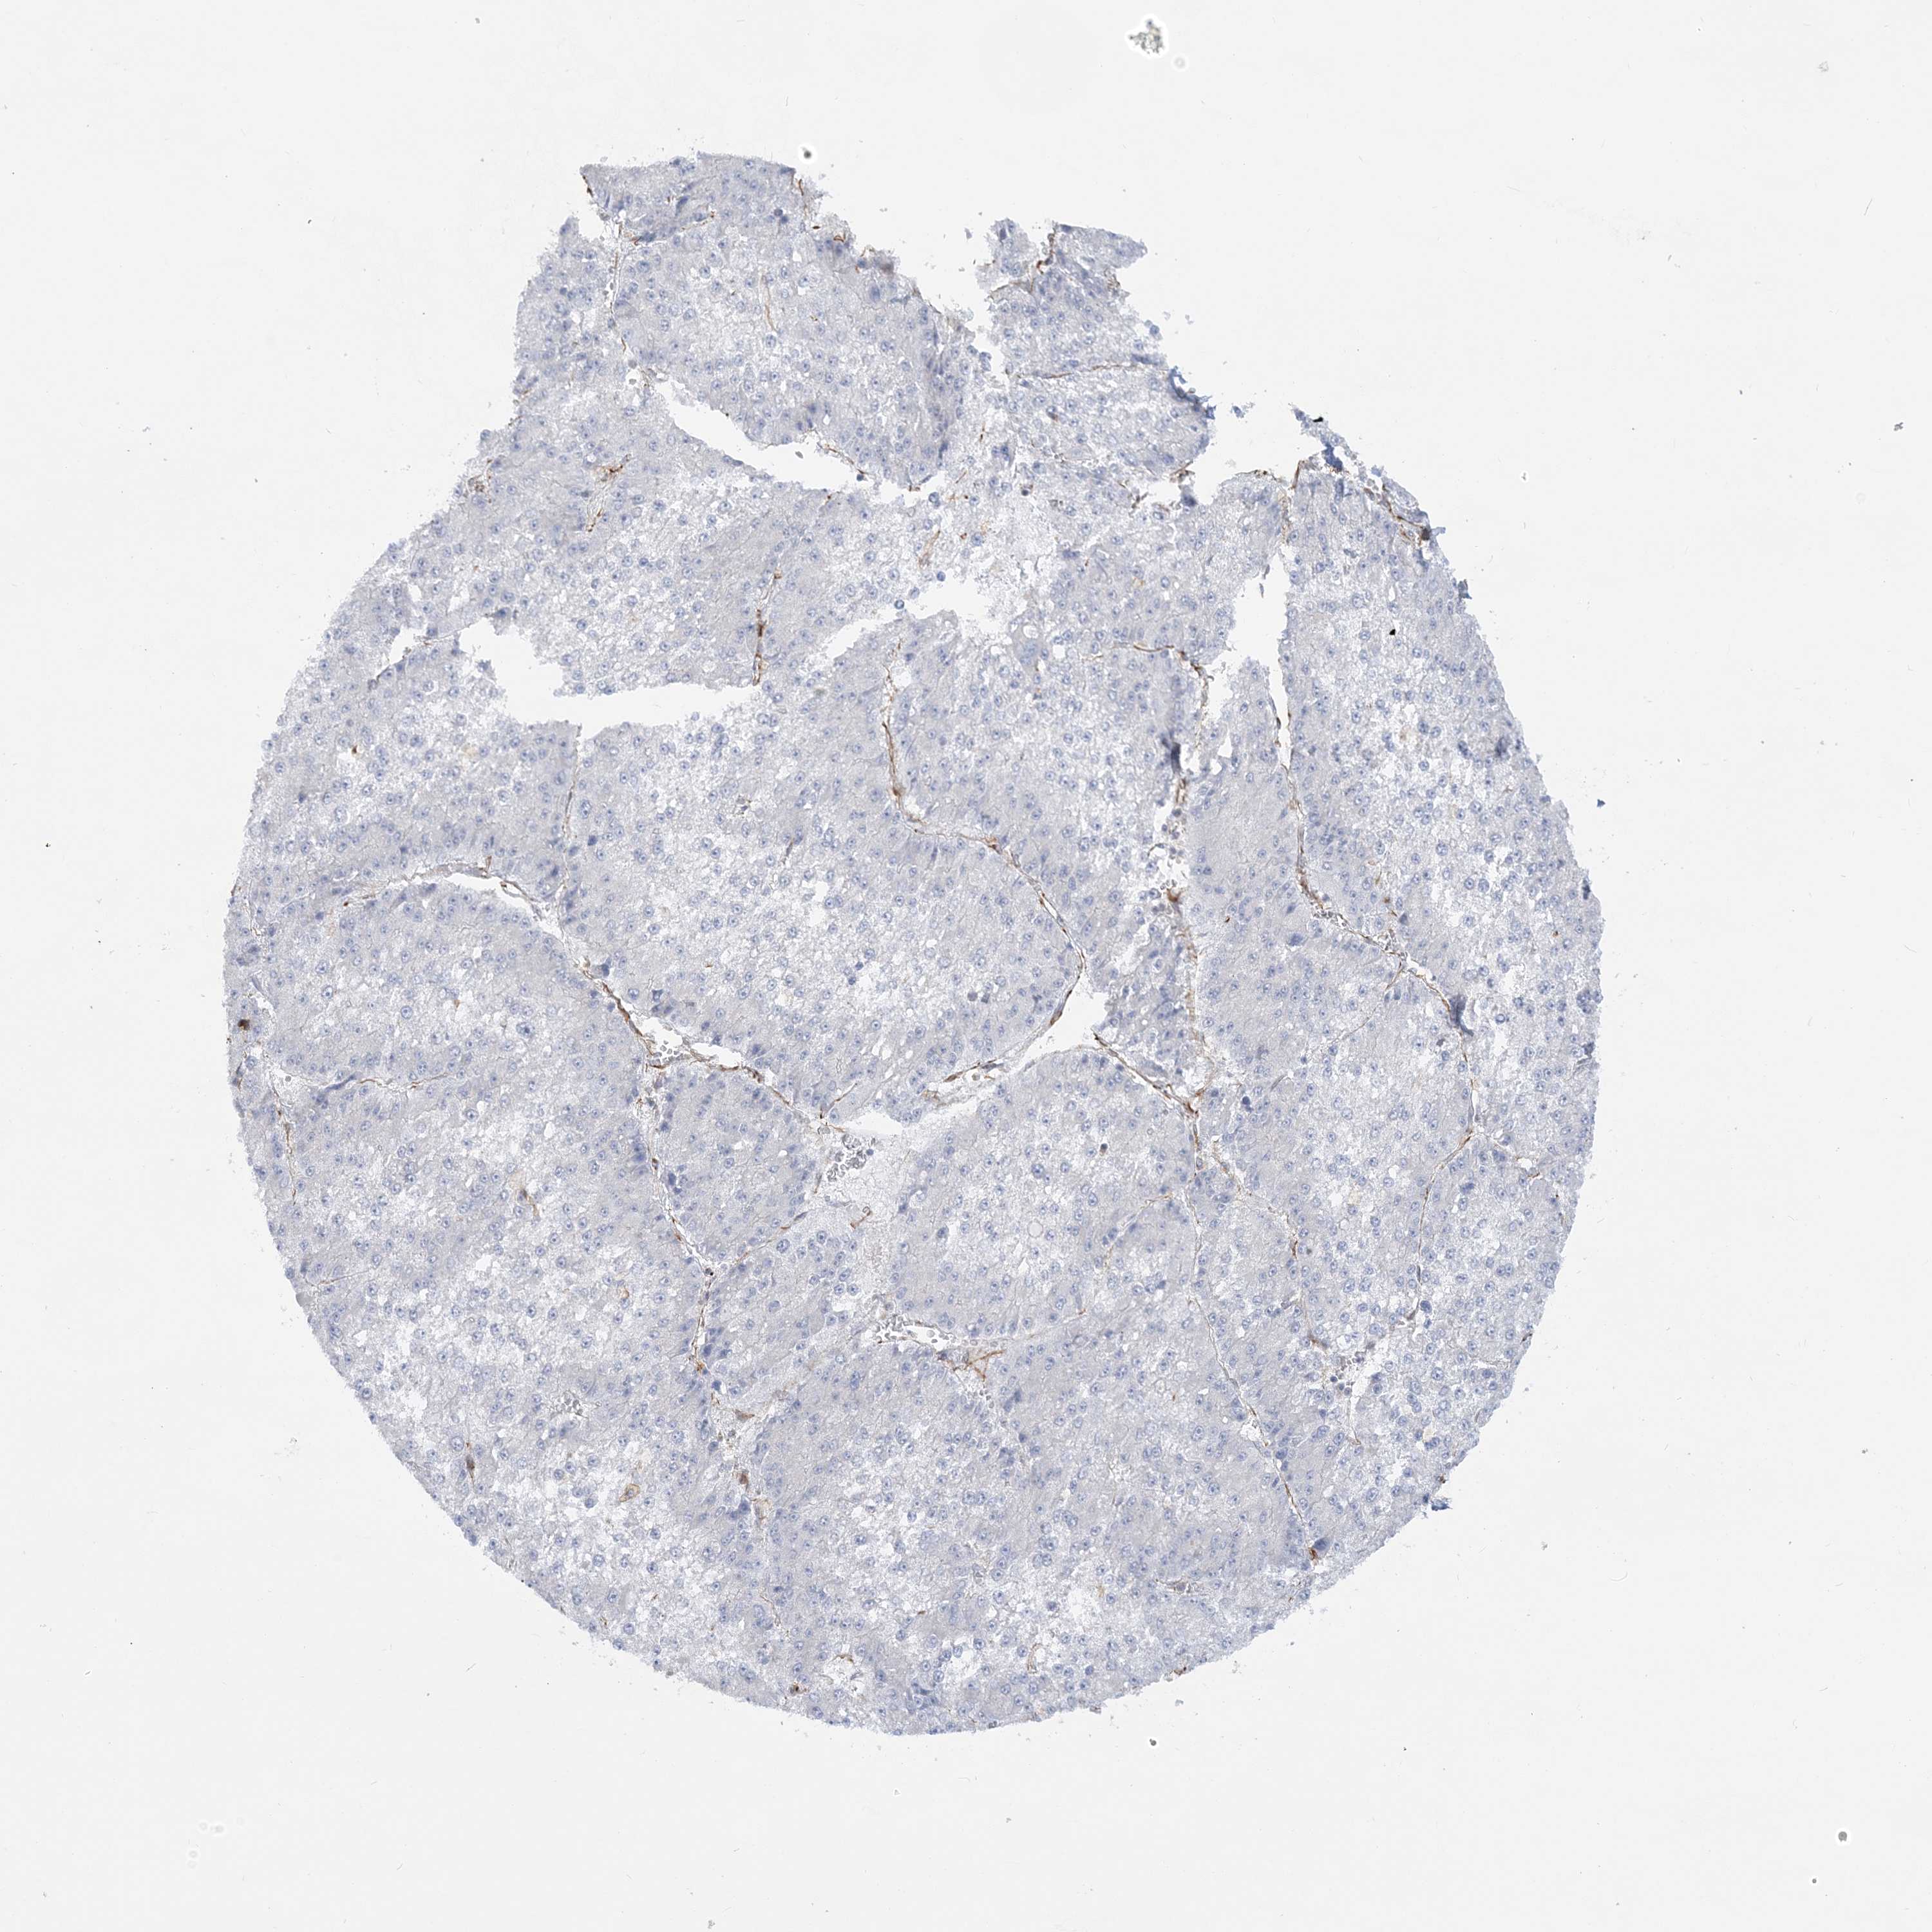

LIVER CANCER - Protein expressioni

A mouse-over function shows sample information and annotation data. Click on an image to view it in a full screen mode. Samples can be filtered based on level of antibody staining by selecting one or several of the following categories: high, medium, low and not detected. The assay and annotation is described here.

Antibody stainingi

Antibody staining in the annotated cell types in the current human tissue is reported as not detected, low, medium, or high, based on conventional immunohistochemistry profiling in selected tissues. This score is based on the combination of the staining intensity and fraction of stained cells.

Each image is clickable and will lead to virtual microscopy that enables deeper exploration of all samples and also displays staining intensity scores, fraction scores and subcellular localization as well as patient and tissue information for each sample.

Antibody HPA036560

Antibody HPA036561

Staining

High

Medium

Low

Not detected

Intensity

Strong

Moderate

Weak

Negative

Quantity

>75%

75%-25%

<25%

None

Location

Nuclear

Cytoplasmic/membranous

Cytoplasmic/membranous,nuclear

Cholangiocarcinoma

Carcinoma, Hepatocellular, NOS